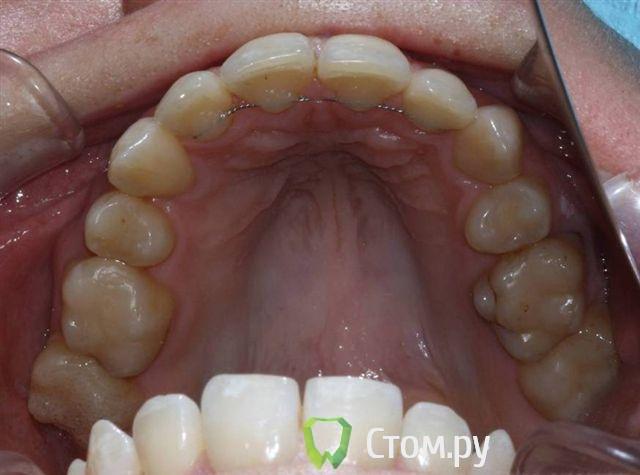

Александрстрад Опубликовано 8 ноября, 2011 Поделиться Опубликовано 8 ноября, 2011 Уважаемые доктора! Потерял и веру и надежду в возможность решения проблемы у своей жены. Одел на нее брекеты у знакомых ортодонтов в Москве, результаты, которых видел. В процессе лечения консультировался и ЦНИИСЕ у Арсениной и у других докторов, работал в крупнейшей медицинской компании, доступ к врачебной базе был очень большой. В процессе лечения все говорили что лечение идет нормально, а когда сняли брекеты ужаснулись все. Хронология лечения у ортодонта описана ниже, включая проблемы, которые мы получили после лечения.1. Показания к лечению брекет-системамиХруст при жевании в правом суставе.Замещение отсутствующего на нижней челюсти пятого зуба справа в течение 10 лет. В результате отсутствия 5-го зуба: наклон 4-го и 6-го по направлению друг к другу, резорбция (убыль) костной ткани на челюсти на месте отсутствующего зуба.Левый клык на верхней челюсти выходил из зубного ряда.Смешение центра верхней челюсти влево.Правый клык до момента начала лечения на верхней челюсти не вышел, находился в состоянии ретинированного, т.е. не вышел.2. Этапы леченияНачало лечения брекет системой - 2006 год.Снятие брекет системы 2009 год.Что было сделано:1. Левый клык на верхней челюсти был поставлен в зубной ряд.2. По отсутствующему 5-му зубу на нижней челюсти - доктор принял решение по замещению, путем передвижения зубов на нижней челюсти вправо,что и было проделано.3. Через 2 года ношения брекет-системы было принято решение по вытаскиванию левого ретинированного клыка.Был удален 3-ий зуб и в освободившееся пространство был вытянут клык.В результате данного объема работ и некорректной работы доктора,были завалены внутрь зубы на верхней челюсти - левая сторона, начиная от 1-го и далее, от резцов до жевательных.Также после сделанного панорамного снимка выяснилось, что произошло рассасывание корней 4-х фронтальных зубов на верхней челюсти более 65%.4. Также в процессе лечения был потерян 6-ой зуб на нижней челюсти слева. Проблемы сейчас1. Хруст в челюсти при жевании и зевании не прекратился, а появился и слева.2. Заваленная левая часть зубов на верхней челюсти не позволяет смещать нижнюю челюсть влево,тем самым перегружаются жевательные мышцы справа, в результате бывают головные боли и боли в мышце при жевании.3. Рассасывание 4-х верхних зубов.4. Расстояние справа между верхней и нижней челюстью на данные момент 3 мм. Сделали после снятия бректов исселдование у ортопеда, заключение ниже. Ее приговор - ТОТАЛЬНОЕ протезирование.Жене 36 лет, она даже слышать об этом не хочет. ПОМОГИТЕ РЕШИТЬ ПРОБЛЕМУ, НАДЕЖДЫ БОЛЬШЕ НЕТ. Заключение ОРТОПЕДАTreatment objectives∙ Transversal and sagittal discrepancy- make passive centic arch of upper jaw fit to active centric active lower jaw∙ First interference contact in RP on 24-34 and 37-27 with disocclusion for + 2 mm. Rp= 0=-2 mm, and till last contact =-4mm on incisal pin, so increase IP for =+3mm∙ Muscle problems∙ Change OPI on right side from 15 degrees to 20 degreees and change Cui right side to∙ Increse LFH +3 mm on incisal pin∙ Curve of Spee will be accentuated for 36∙ Steep condyle- decreased radius curve of Spee∙ Cui for 13 is not more than 55 degrees∙ Curve of Spee=Curve of wilson for 36 and 46∙ Rotation of mesial cusp of 6 down- change OPI for 36 – rotate 36 with mesial contact point OPI 6 = 35 degrees for DOA=12 degrees Ссылка на комментарий

Александрстрад Опубликовано 10 ноября, 2011 Автор Поделиться Опубликовано 10 ноября, 2011 Непонятны причины такой резорбции корней резцов...Да,задача номер один-стабилизация ВНЧС. Я бы пока не думал о повторном ортодонт.лечении,учитывая степень резорбции корней. По стабилизации - ортопед начала двигаться в этом направлении, для чего была проведена большая диагностика за 100 000 руб. в артикуляторе, сделаны слепки, снимки челюсти в госпитале МВД (описания делала сама начальник отделения, по отзывам одна из самых квалифицированных в Москве). После чего она вынесла решение по тотальному протезированию для нормализации положения суставов.Если будет возможность посмотреть презентацию с расчетами, которая была сделана и является финальным результатом диагности, готов отправить на почту. Был бы очень признателен.По тотальному протезированию - это катастрофа. Резорбция корней вызвана чрезмерной нагрузкой, в момент вытягивания правого ретинированного клыка. Когда его тянули резинки закрепляли за левую часть верхней челюсти, чтобы инициировать движение клыка, в результате и правую сторону челюсти "завалили" внутрь, а также получили огромную нагрузку на все фронтальные зубы, результатом чего и стала резорбция.Сначала доктор сам не поверил, что это произошло и может произойти в 33 года. Не рассматривался организм в целом при лечении и заболевания, а по факту у жены артрит/артроз. Ссылка на комментарий